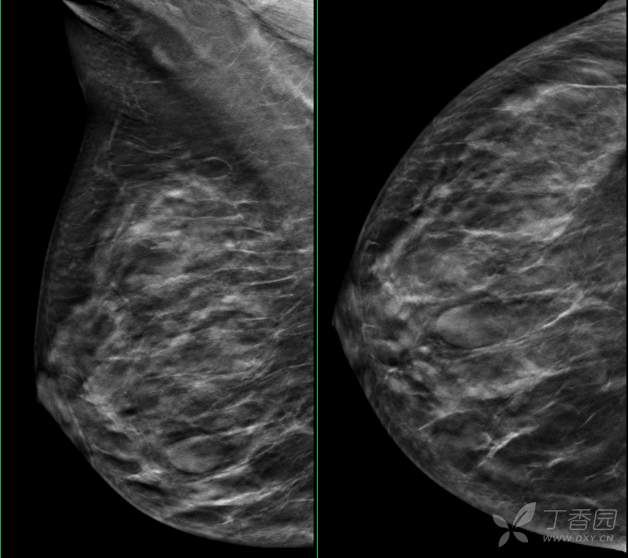

乳腺X线摄影

乳腺X线:左乳外上象限可见肿块,形态尚规则,边缘可见分叶,范围约12mm × 10mm。

乳腺X线检查

2、乳腺X线检查显示右乳中下象限肿块,形态尚规则,部分边界清晰,范围约33mm*13mm。BI-RADS 3类。